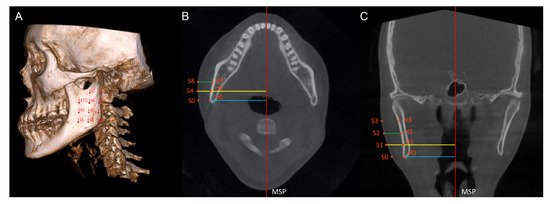

| H0 | Point corresponding to the Gonion point on the deviated side. |

| H1 | Point located on the external cortical bone of the mandible, on the same coronal slice as H0, and 10 mm above H0 on the axial slice. |

| H2 | Point located on the external cortical bone of the mandible, on the same coronal slice as H0, and 10 mm above H1 on the axial slice. |

| H3 | Point located on the external cortical bone of the mandible, on the same coronal slice as H0, and 10 mm above H2 on the axial slice. |

| H4 | Point located on the external cortical bone of the mandible, on the same axial slice as H0, and 10 mm anterior to H0 on the coronal slice. |

| H5 | Point located on the external cortical bone of the mandible, on the same coronal slice as H4, and 10 mm above H4 on the axial slice. |

| H6 | Point located on the external cortical bone of the mandible, on the same coronal slice as H4, and 10 mm above H5 on the axial slice. |

| H7 | Point located on the external cortical bone of the mandible, on the same coronal slice as H4, and 10 mm above H6 on the axial slice. |

| H8 | Point located on the external cortical bone of the mandible, on the same axial slice as H4, and 10 mm anterior to H4 on the coronal slice. |

| H9 | Point located on the external cortical bone of the mandible, on the same coronal slice as H8, and 10 mm above H8 on the axial slice. |

| H10 | Point located on the external cortical bone of the mandible, on the same coronal slice as H8, and 10 mm above H9 on the axial slice. |

| S0–S10 | Extension of hard tissue point (H0 to H10) perpendicularly from the MSP to the outermost soft tissue contour of the face. |

| H’0–H’10 | Hard tissue points on the non-deviated side of the mandible, corresponding to H0 to H10. |

| S’0–S’10 | Soft tissue points on the non-deviated side, corresponding to S0 to S10. |

| Hard tissue prominence (mm) | The perpendicular distance from a hard tissue point to the MSP. |

| Soft tissue prominence (mm) | The perpendicular distance from a soft tissue point to the MSP. |

| Soft tissue thickness (mm) | The distance between a hard tissue point and a soft tissue point perpendicular to the MSP. |

| Menton deviation (mm) | The perpendicular distance from the menton point to the mid-sagittal plane. |